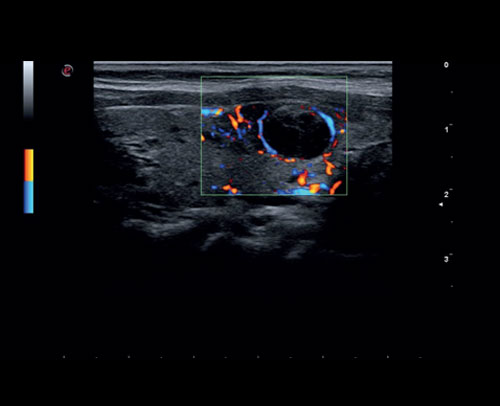

Léze štítné žlázy, zobrazení 2D s barevným dopplerem.